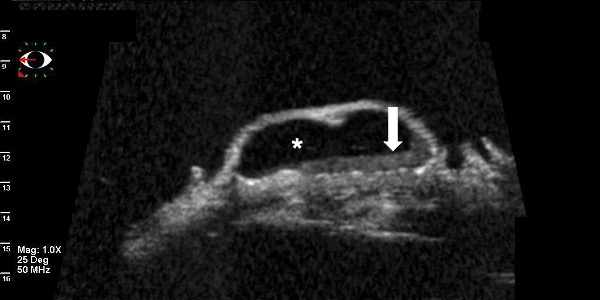

4B. UBM cross-section of the cystic lesion, hyporreflective content (*) and an inferior deposit with punctiform particles (thick arrow). The posterior limit with the sclera is easily detected. Photo courtesy of Norma Allemann PhD. Department of Ophthalmology, Federal University of São Paulo, Brazil.